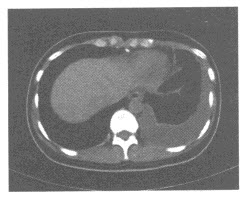

女,36岁,左胸部疼痛不适5天,CT图像如图,应诊断为()

A、胸膜间皮瘤

B、胸腔积液

C、腹腔积液

D、胸膜增厚

E、胸膜钙化斑

B